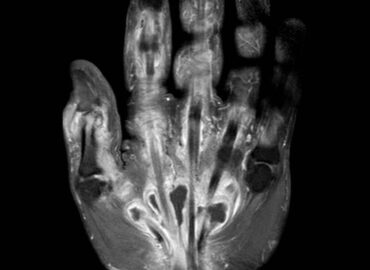

Noviembre 2025. Hospital Italiano

Masculino de 61 años. Masa dolorosa en cara anterior de pie derecho.